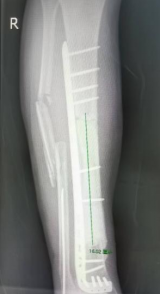

在3D打印的金属假体完成后,吴大爷再次入院。2025年12月周翔教授再次亲临我院指导手术,经过掀起原移植的皮瓣,取出临时植入的骨水泥及固定的钢板,在胫骨远近端进行精准截骨,顺利安装好3D打印的胫骨金属假体。不到2小时,即按术前规划成功完成了这个“私人定制”式的手术。

△3D打印定制式胫骨金属假体(可拆分)。